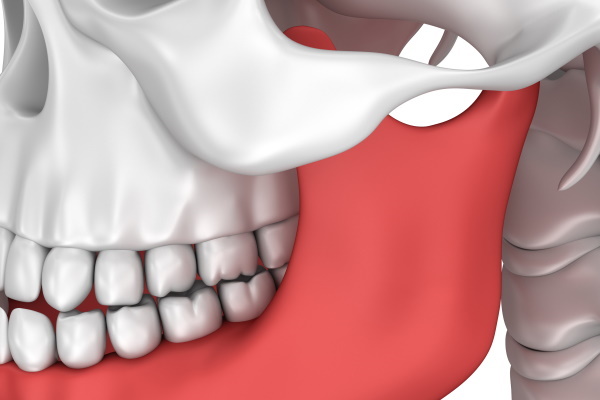

顎関節症とは?

顎の関節、周囲の筋肉、噛み合わせなどに過度な負担がかかり、痛みや機能障害を起こす状態の総称です。10〜30代の女性に多く見られますが、年齢・性別に関係なく、ストレスや生活習慣の積み重ねで発症します。